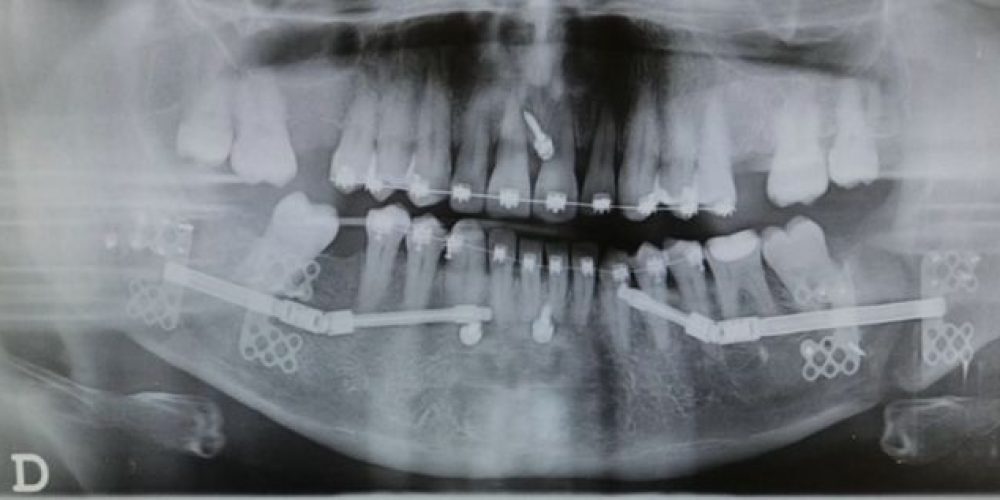

Categories Cirugía Maxilofacial Barcelona Posted on 04/06/2018 Paciente con apnea de sueño y mandíbula pequeña